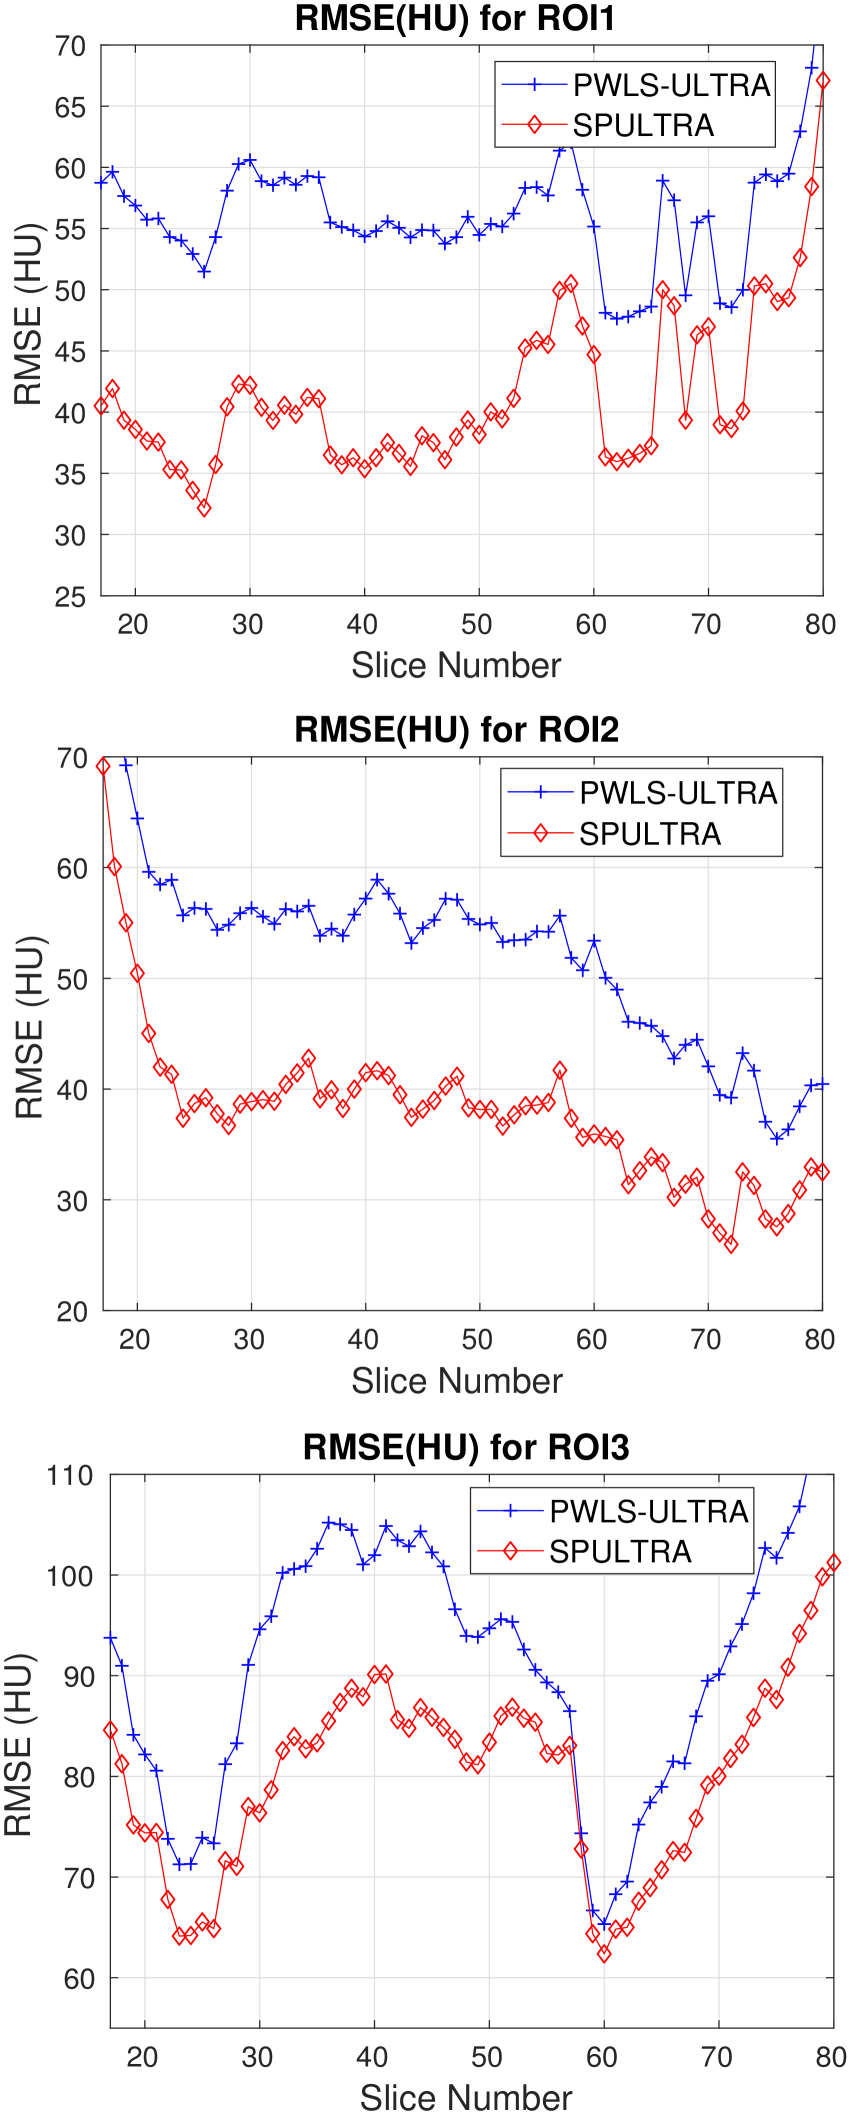

Fig. 4 shows the reconstructed images and the corresponding error images for PWLS-EP, PWLS-ULTRA, and SPULTRA, at and . Compared to the PWLS-EP result, both PWLS-ULTRA and SPULTRA achieved significant improvements in image quality in terms of sharper reconstructions of anatomical structures such as bones and soft tissues, and suppressing the noise. However, the PWLS-ULTRA method introduces bias in the reconstructions, which leads to larger reconstruction errors compared to the proposed SPULTRA method. In Fig. 4, we marked three 3D ROIs in the axial plane, i.e., ROI 1, ROI 2, and ROI 3. Fig. 5 shows the zoom-in images of a 3D plot of ROI 1, and those of ROI 2 and ROI 3 are shown in the supplement. We also plot the evolution of RMSE through the axial slices of the three 3D ROIs in Fig. 6. The figures demonstrate that SPULTRA clearly outperforms the competing PWLS-EP and PWLS-ULTRA schemes.

The RMSE improvement of SPULTRA over PWLS-ULTRA can be more clearly observed from Fig. 3 that shows the RMSE evolution with the number of outer iterations under different dose levels. At low-doses, SPULTRA decreases the RMSE more quickly (from the same initial value) and to much lower levels than PWLS-ULTRA. Fig. 3 shows that to achieve the same RMSE as PWLS-ULTRA at 600 outer iterations, SPULTRA takes 487, 365, 251 and 133 outer iterations under , respectively.